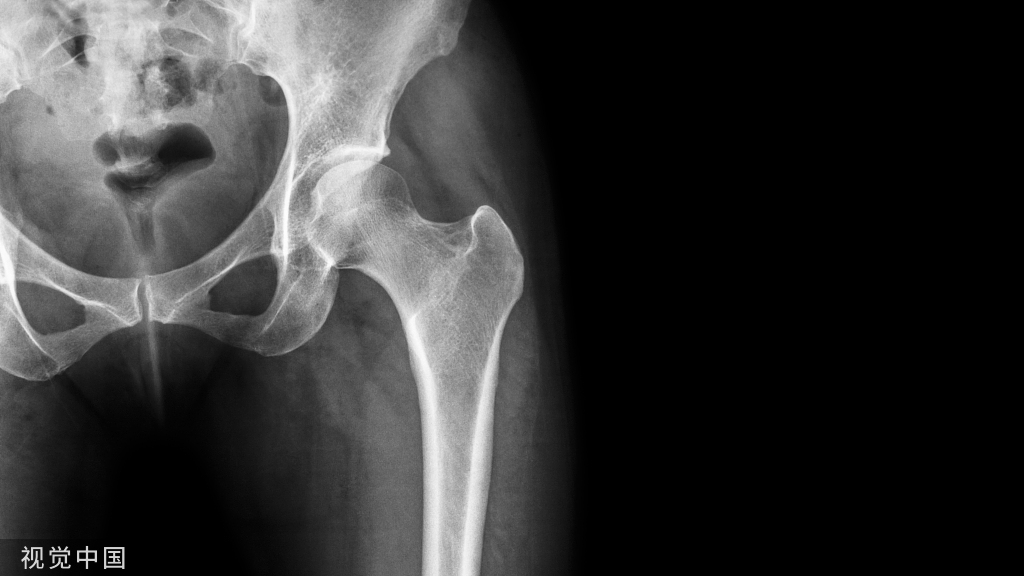

使用 2018 年中华医学会骨科分会关节外科学组制定的《膝骨关节炎阶梯治疗专家共识(2018年版)》中的诊断及分级标准(共识建议)。

诊断膝骨关节炎需要参考膝关节X线片及MRI等影像学资料(共识建议)。参考中华医学会骨科分会关节外科学组制定的《膝骨关节炎阶梯治疗专家共识(2018年版)》

目前,对 KOA 的分级方法是根据 X 线改变的Kellgren & Lawrence分级(简 称 K-L分 级),见表2。